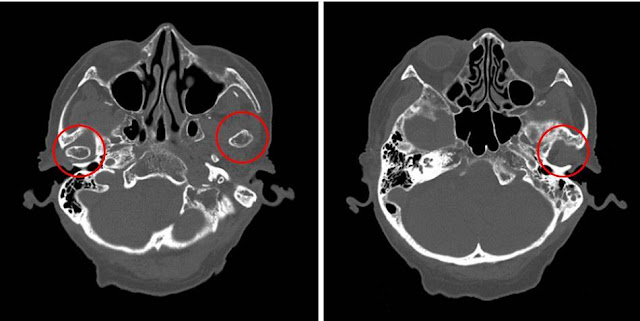

画像クイズ(転倒後)

左側顎関節脱臼

と診断(図の

赤丸部分

の左右差に注目)

開口や閉口は可能で,疼痛もなく食事摂取も可能であった

下顎は無歯顎で義歯を使用しているため咬合も支障なし

整復は行わずに経過観察(今回の転倒との関連は不明)

頭部CTでは顎関節も忘れずにチェック ➜